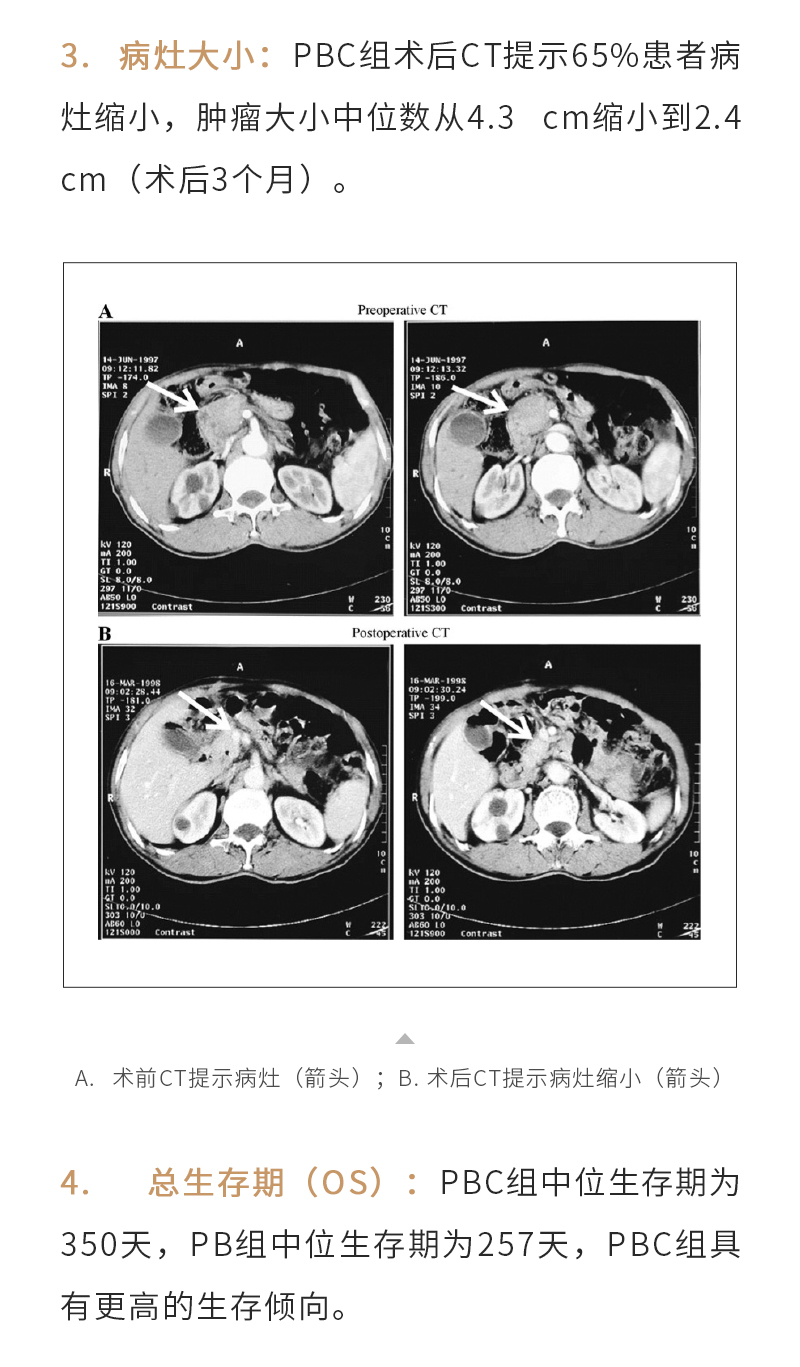

產(chǎn)品介紹

新聞動態(tài)